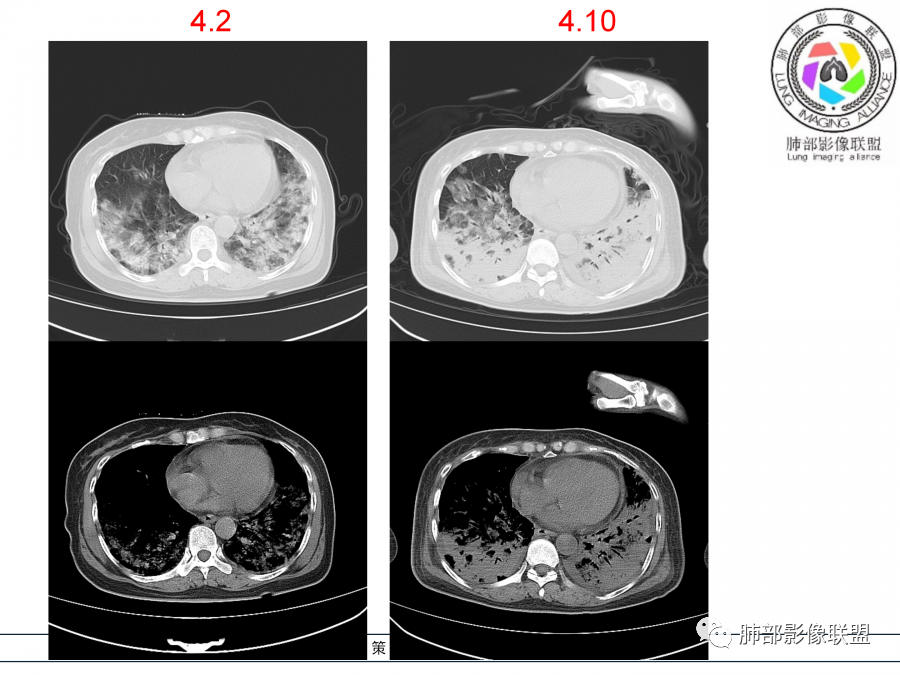

影像,第一次双肺中下叶胸膜下多发斑片状实变影,部分融合成,周围散发磨玻璃影,磨玻璃影内可见小叶间隔及小叶内间隔增厚,病变平行于胸膜,第二次间隔8天,双肺实变影明显进展,有重力作用,支气管近端堵塞,进展较快,临床有发热,血沉高,狼疮SLE阳性,考虑1:OP(机化性肺炎)2:SLE相关肺炎,建议支气管镜灌洗液病原学检测。

➢患者7天前起因受凉后出现阵发性咳嗽,无明显时间规律性,咳黄白粘痰,发热,体温最高达39.5℃,伴鼻塞、流清涕,。两肺下叶背段,后基底段为主的渗出性的病变,短时间内病变明显的增多,双侧胸腔积液,狼疮全套抗R0/SS检测阳性,考虑狼疮性肺损,机化性肺炎?鉴别结核

老年女性,高热,双肺下野近胸膜下片状高密度影,呈横向融合,双侧对称,抗炎治疗无效,复查病变进展明显,考虑狼疮SlE阳性结缔组织病相关的肺炎。

老年女性,咳嗽咳痰伴发热7天,白细胞不高,血沉快,降钙素原不高。其他化验未见明显异常,狼疮全套抗Ro/SSA阳性,双肺野靠近胸膜下磨玻璃实变影,支气管通畅,有充气征,沿胸膜下分布,有细网格征,7天后进展明显,实变影加重,胸膜肥厚,胸水不明显,心包少量积液?抗感染治疗无效,考虑非感染性疾病可能性大,结缔组织相关性肺病?狼疮性肺炎?机化性肺炎?鉴别病毒性肺炎。

老年女性,咳嗽咳痰发热7天。无气促。白细胞计数不高,PCT稍高,PPD(+),抗Ro/SSA阳性。CT:双肺野靠近胸膜下磨玻璃实变影,支气管通畅,有充气征,沿胸膜下分布,有细网格征。予抗生素治疗,8天后复查胸部CT见病灶范围扩大,实变影加重,胸膜肥厚,胸水不明显。抗感染治疗无效,考虑有:1.非感染性疾病:结缔组织相关性肺病,支持点:肺部CT表现为间质性炎症病变,抗RO/SSA(52)阳性;2.病毒性肺炎:患者无气促症状,可能性小;3.肺结核。

两肺胸膜下磨玻璃影➕实变影,非叶段分布,基底部明显,抗感染治疗无效,迅速进展伴胸腔积液。无明显低氧血症。

狼疮肺炎的病理是DAD➕ 肺出血,影像可以表现ggo➕ 实变,胸水常见,抗感染无效,加上影像是符合的,可以考虑,不过目前只有一项rra52抗体阳性,临床诊断依据不足,需要进一步证实,